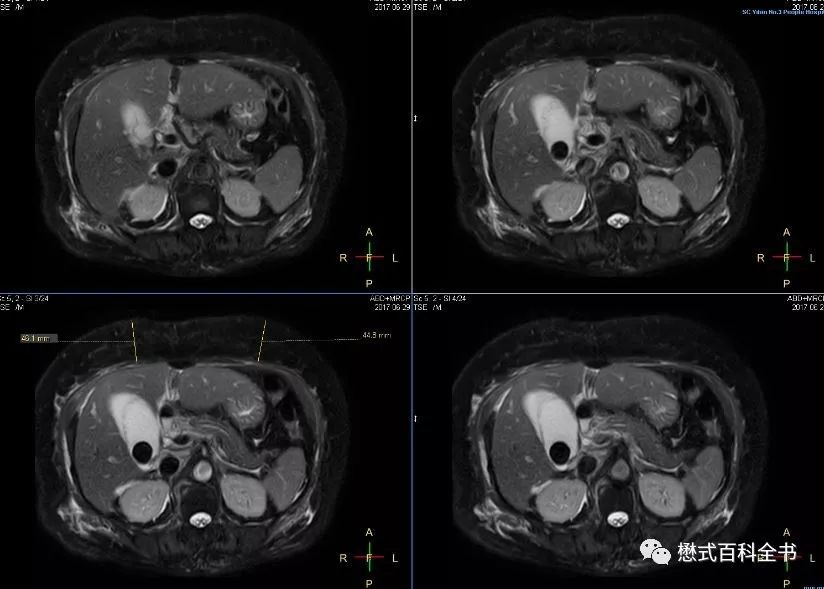

图27:胰头区囊性占位,肝内胆管、胰管扩张(Ingenia 1.5T图像)

有的时候,如果要诊断胆囊结石或者胆管结石,相对难度不大。明显的结石,经常在常规的横轴位T2WI或者冠状位T2WI上即可显示。难度大的在于胆总管下段的占位或者不确定的梗阻。